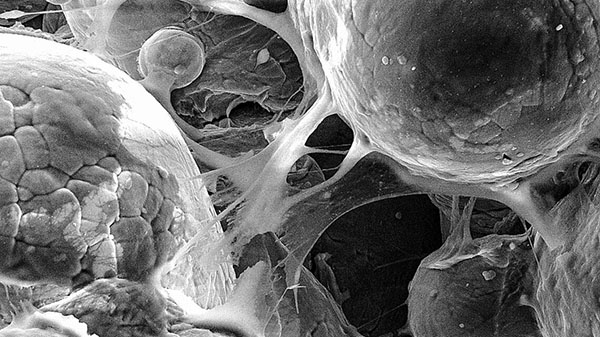

这张图片显示的是细胞黏附在由冷喷3D打印生成的钛合金上,展示出材料的生物相容性。 (图片来源:Cornell University)

这种被称为“冷喷涂”的技术形式使得多孔结构具有足够的机械强度,比传统制造工艺制造的类似材料坚固40%。这种结构的小尺寸和多孔性使其特别适合于打造生物医学组件,比如置换的关节。

区别于传统校准方式,Moridi的团队使用计算流体动力学确定了一个速度,这个速度稍稍慢于临界速度。当粒子以这种稍微慢一点的速度发射时,会形成更加多孔的结构,此形态对于生物医学应用非常理想,比如用于膝关节或髋关节的人工关节,以及颅面部移植。

Moridi说:“如果我们将这种多孔结构植入体内,骨头就可以在这些多孔内生长,形成生物固定。这有助于降低假体松动的可能性。这很重要。如果假体松动引起很大的疼痛,患者必须进行多次修正手术来取出植入物。”